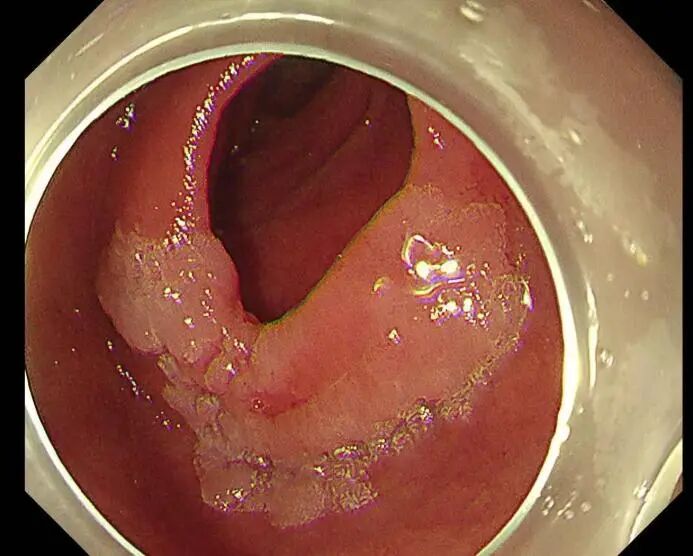

手术开始,尽管十二指肠降部空间有限,病变较大,且十二指肠部位血供丰富,但在SPEED技术的辅助下,徐美东教授用稳定的控镜和精妙的微操,如“庖丁解牛”般逐步推进,边注射边剥离,全程视野清晰可见,最终仅耗时半小时将该病变整体剥离并完整取出,完成这场“刀尖上的舞蹈”。创面干净、几乎无出血,没有丝毫肌层损伤,堪称内镜手术的“完美范本”。

4-切除后的创面

6-切除下来的标本